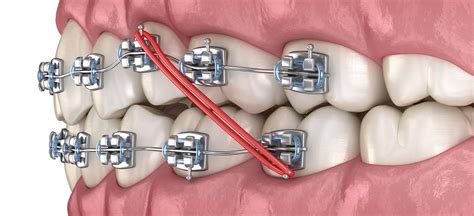

Las gomas, elásticos o ligaduras intermaxilares son un componente importante durante un tratamiento de ortodoncia y, normalmente, se usan antes o durante el tratamiento. Este tipo de gomas intermaxilares se utilizan para generar fuerzas específicas entre la mandíbula y el maxilar con el fin de corregir desalineaciones dentales o problemas de maloclusión. Su uso es especialmente útil cuando se trata de mejorar la interacción entre la mandíbula y el maxilar y para mejorar estéticamente el perfil facial.

La función que desempeñan las ligaduras intermaxilares en ortodoncia depende del diagnóstico de cada caso y de la planificación personalizada del tratamiento. Normalmente, las gomas de los brackets o alineadores sirven para realizar pequeños movimientos en los dientes o cambiar la posición de la mandíbula o el maxilar para conseguir los resultados esperados, tanto a nivel estético como funcional.

Cuando se trata de corregir la posición de los huesos, los motivos más comunes para usar elásticos intermaxilares son la corrección de casos de sobremordida o prognatismo. La colocación adecuada de las gomas en la ortodoncia puede desplazar el maxilar o la mandíbula a la posición óptima para conseguir una oclusión adecuada.

Por otro lado, cuando hablamos de movimientos en los dientes, los elásticos intermaxilares también pueden utilizarse para cerrar espacios entre piezas dentales o para mover un diente en concreto, de manera que permite una mejor alineación dental.

El efecto de los elásticos en ortodoncia consiste en la aplicación selectiva de una fuerza sobre la mandíbula o el maxilar y los dientes que, gradualmente, provoca movimientos y correcciones planificadas. Es importante llevar las gomas con regularidad y cambiarlas tal y como el ortodoncista indique para alcanzar los resultados en el tiempo esperado.